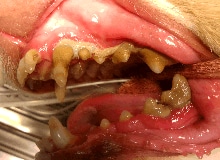

If we do not regularly disinfect our mouths and brush away the plaque, the plaque will mineralize into tartar (also called calculus – gritty material that the dental hygienist scrapes away). Tartar is solid and gritty, and blocks oxygen from bathing the outer tooth and thus MarVistaVet) changes the nature of the bacteria that can live around the tooth. Inflammation and tenderness result in the gingival sulcus.

Tartar builds up covering most of the crown of the tooth as well as the attachment of the tooth root below the gum.